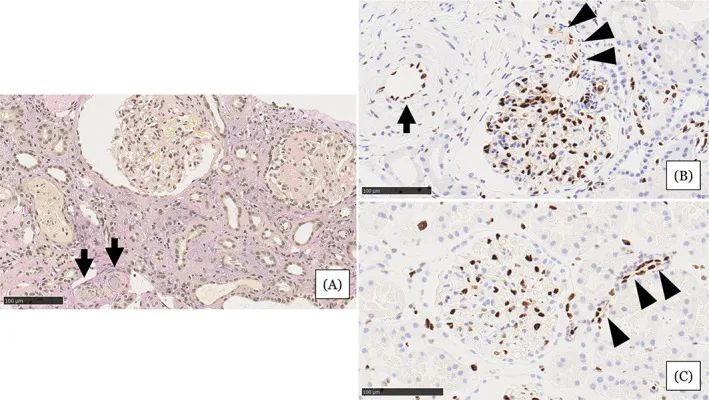

圖注:在住院第31天進行的腎活檢結果。A,顯示小動脈被粘液性內膜增厚(箭頭)堵塞,腎小球萎縮,毛細血管壁起皺,嚴重的間質單核細胞浸潤伴腎小管損傷。B,EC細胞核的缺乏在小動脈(箭頭)中很突出。在相鄰的小動脈(箭頭)中注意到不同大小的不規則細胞核。C,EC的等距核在血壓正常的腎臟供體的腎臟小動脈中形成有序的線。比例尺 =100μm